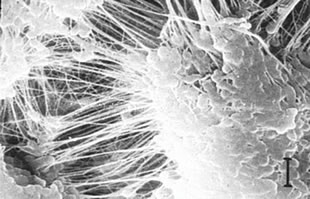

Substantial wear reductions have been made with crosslinking technology when compared to traditional poly. However, crosslinking compromised the material's properties and created a new set of problems in dealing with strength issues.

Over all, volume of wear generation is less with XLPE poly. However, there is growing concern on the behavior of the smaller and potentially more reactive particles generated with crosslinking of polyethylene.

It has been almost three decades since Willert first describe the problem of polyethylene wear leading to peri-prosthetic inflammation, granuloma, bone resporption and implant loosening.3 Since then many publications have discussed this subject.4,5,6,7 Issues have been raised with current materials (MoM, CoC, MoP) from squeaking, high trace elements, strength and implant stability.8,9,10,11,12,13,14

The following are examples of polyethylene failed devices and induced osteolysis